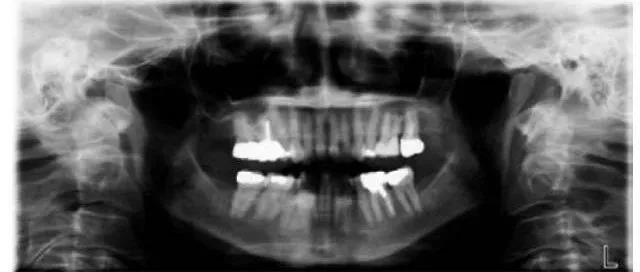

全景片就是可以在一张胶片上可以完整、清晰地显示上颌骨、下颌骨全貌,上下颌牙列情况,牙槽骨情况,能清晰显示上颌窦腔、窦壁、窦底情况,以及颞颌关节情况,并对颌骨周围疾病的诊断提供帮助。

因为全景片可以精确测定牙齿倾斜角度、牙周软组织情况、牙根情况、牙槽骨质情况,解剖形态的精确测量为医生术前的诊断分析与设计提供全景样图像依据,口腔医生借此能更好地为患者设计治疗方案。

拍摄全景片是口腔治疗之前很重要的一个检查过程,医生通过全景片可以观察到牙齿的健康状况,是否有隐形龋齿、埋伏阻生牙、多生牙、牙槽骨吸收、牙龈萎缩、口腔内是否长有瘤体等。在做牙齿种植、牙齿矫正、牙齿修复、智齿拔除等之前,均需要拍摄口腔全景片。